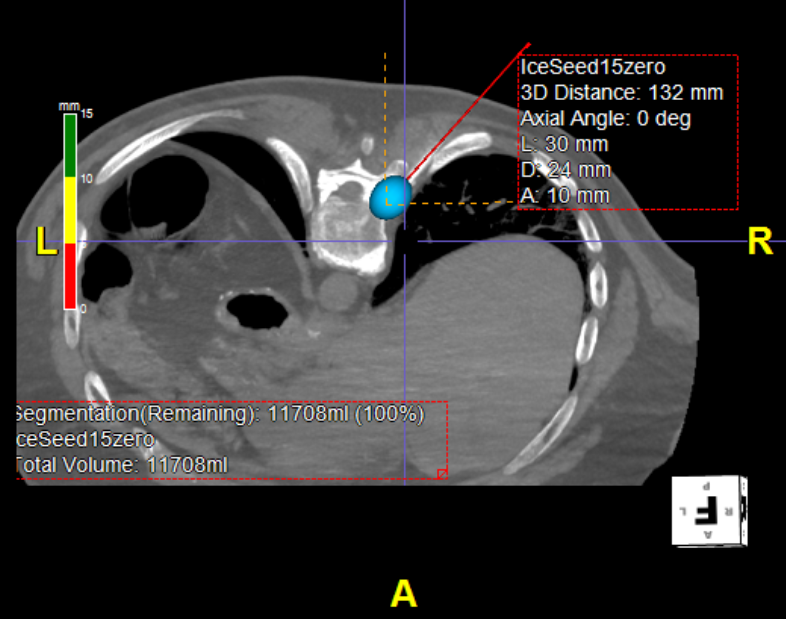

Cryoneurolysis

Extreme low temperature (-40 degrees Celsius) can be used to turn off nerves and is more potent than RFA. Our special cryoprobes can be placed adjacent to the target nerve, and a large ice ball grown to encompass the nerve, providing long lasting relief from nerve related pain. This is particularly useful in the cancer pain setting.